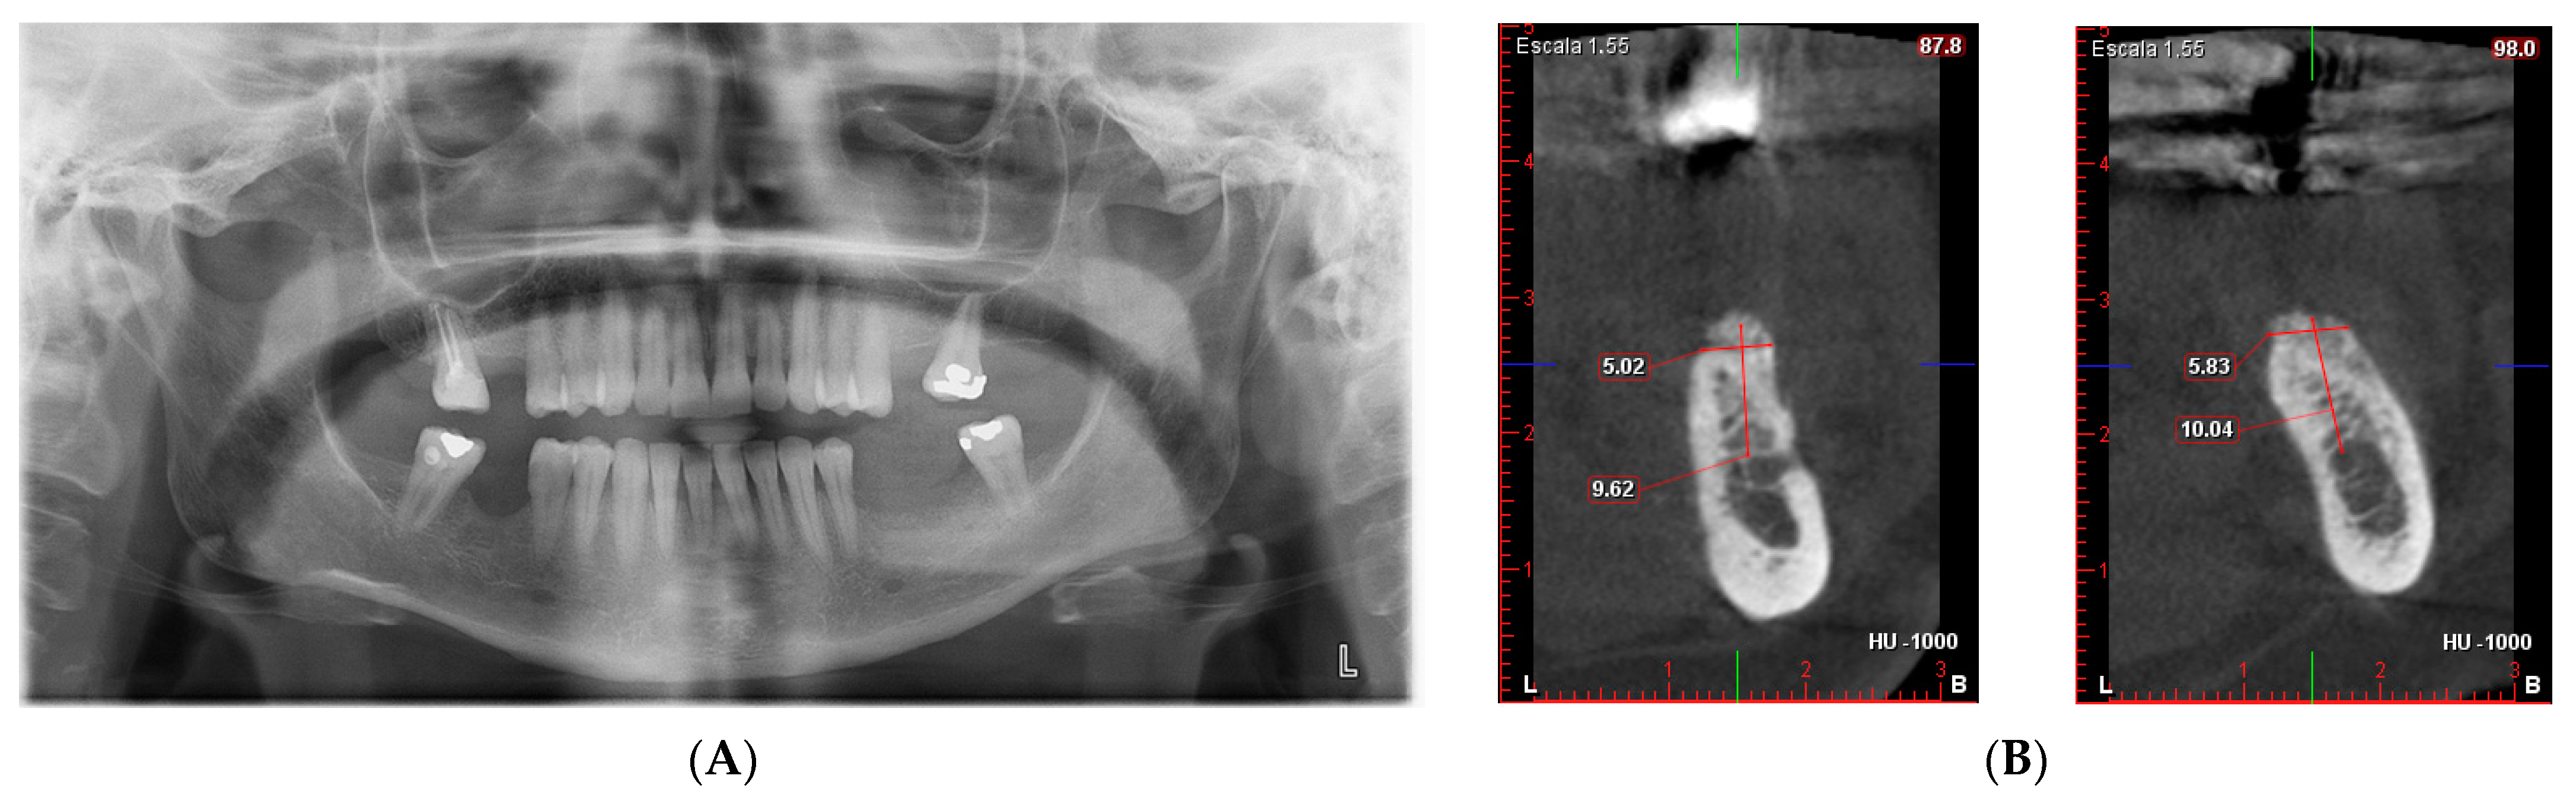

- First surgery: Local anesthesia Articaine 4% with epinephrine (1:100,000) was administered. An intrasulcular incision was made from the mesial of 3.3 to the distal of 3.7, continuing along the anterior border of the external ramus of the mandible. Periosteal incisions were made to mobilize the vestibular flap and the upper fibers of the mylohyoid muscle were disinserted to passivate the lingual flap and thus obtain a tension-free closure (Figure 3). We then checked the position of the mesh and proceeded to collect bone from the ascending branch using the bone scraper (Micross®, Selecdent, Barcelona, Spain) (Figure 4A). Cortical perforations were made to promote bleeding (Figure 4B). We mixed the autologous bone with the xenograft (Tioss®, Sanhigia, Bujaraloz, Spain) in a 70:30 ratio, inserted it into the mesh, and the mesh was placed in the defect.

- After 7 and a half months, the Avinent® 3.8 × 8.5 implants were placed in position 3.5 and 4 × 8.5 in position 3.6 (Figure 11). The torque of the implants was greater than 45 N/cm. The ISQ of both implants was taken, being 82 buccal and palatal for the implant in position 3.5 and an ISQ of 57 buccal and palatal for the implant in position 3.6. The bone gain obtained was 1.84 and 1.92 mm in width and 4.2 and 3.78 mm in height for positions 3.5 and 3.6. Simultaneously with the placement of the implants, a bone biopsy was performed between the implants, using a 2 mm bone trephine (Sanhigia, Bujaraloz, Spain) (Figure 12). Three months after the placement of the implants, the implants were rehabilitated using metal-ceramic screw-retained crowns.